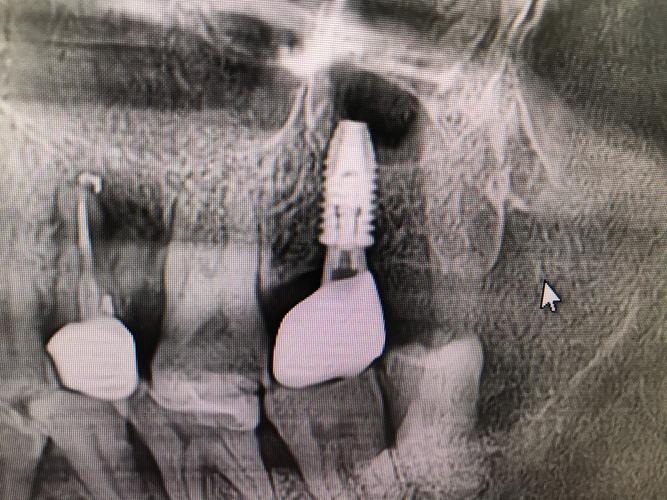

作为植牙术前的“黄金标准”,CBCT通过低剂量辐射获取患者颌骨的三维影像,可清晰显示牙槽骨的高度、宽度、密度,以及神经管、上颌窦等重要解剖结构的位置,在骨量不足的病例中,CBCT能精准测量骨缺损区域,为植骨方案提供数据支持;对于靠近下颌神经管的种植区域,可提前规划种植体植入角度与深度,避免神经损伤。 -

结合CBCT影像与口内扫描数据,导航系统可在术中实时显示种植钻针的位置、角度与深度,医生如同“GPS导航”般控制种植体植入路径,尤其针对复杂病例(如骨量严重不足、全口种植),导航技术可将种植误差控制在0.1mm以内,显著提升手术安全性与成功率。